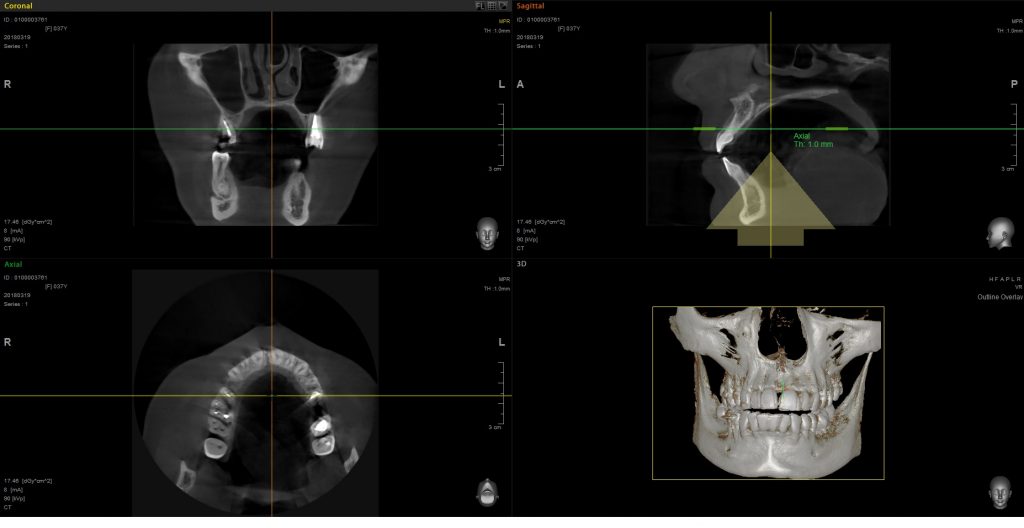

STRESZCZENIE: Tomografia wolumetryczna wiązki stożkowej to nowoczesna i skuteczna klinicznie metoda obrazowania trójwymiarowego. Jak pokazuje przegląd dostępnego piśmiennictwa, może przyczynić się do dokładniejszej diagnostyki i lepszego planowania leczenia w określonych przypadkach klinicznych. Szczególne zastosowanie znalazła w diagnostyce: morfologii kanałów korzeniowych, pęknięć i resorpcji korzeni, stanów zapalnych tkanek okołowierzchołkowych, a także w niektórych przypadkach oceny pozabiegowej skuteczności wypełnienia kanałów korzeniowych. Jej stosowanie wiąże się jednak ze znacznymi kosztami i generuje większą dawkę promieniowania, dlatego decyzja o jej wykorzystaniu powinna zostać podjęta indywidualnie. Nie powinna stanowić metody z wyboru, a jedynie uzupełnienie radiografii klasycznej w konkretnych przypadkach klinicznych.

SUMMAR: Cone beam computed tomography is an innovative and clinically effective 3-dimensional imaging method. This literature review illustrates that it is a highly accurate diagnostic imaging modality that can enable better preoperative treatment planning in specific clinical cases. It is especially applicable in the diagnostics of root morphology, fractures and resorptions as well as in the detection of periapical pathoses and in the [...]